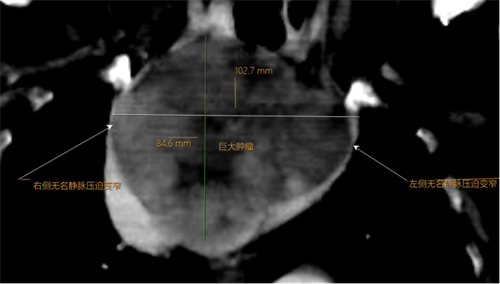

术前CT显示:纵膈巨大占位大小约为10.2cm*9.0cm*8.5cm,邻近气管及大血管明显受压变窄,气管前后径仅为2.5mm(正常成人气管直径约15-25mm)

据了解,李奶奶曾被诊断患有胸腺瘤,多次前往四川省人民医院及四川大学华西医院就诊。由于其身体基础状况较差,且肿瘤巨大(已侵犯大血管及气管),外科切除难度极大,手术风险极高,李奶奶本人也拒绝外科手术切除。此次,因巨大的胸腺肿瘤同时压迫气道和右侧无名静脉,导致李奶奶出现急性呼吸困难和上腔静脉血液回流受阻而昏倒。

术前患者呼吸困难(气管受压插管)、颜面部水肿(上腔静脉阻塞)